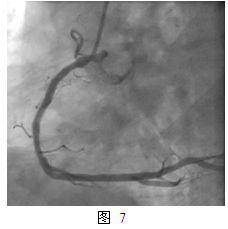

一年后,2013年2月患者再次出现活动时胸痛,特别是在高原地区。第三次住我院,复查冠脉造影:右冠支架内PEB治疗部位再狭窄80%(图5)。本次介入治疗于右冠支架内狭窄部位经球囊预扩张后置入XienceV支架 3.5mm x 23mm, 最大16atm扩张(图6),并用后扩张球囊Quantum 3.5mm x 15mm, 最大24atm 扩张,最终效果满意(图7)。